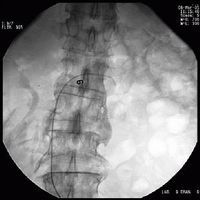

腎活檢治療的關鍵在於早期確診,及時去除誘因和有效的治療。

3、組織學檢查活檢部位的選擇取決於具體疾病,如診斷韋氏肉芽腫,可進行鼻或鼻竇活檢,侵入性小診斷價值又高。

4、腎活檢 除了常規光鏡檢查外,通常需要進行直接免疫螢光染色。免疫介導的肺泡出血綜合徵同時有腎受累時,則腎病理為壞死性腎小球腎炎,組織學改變的程度不同,從輕的系膜增厚至嚴重的新月體性腎小球腎炎,腎動脈血管炎則很少。各種疾病的免疫螢光染色有不同表現,抗基底膜抗體(ABMA)病沿腎小球基底膜有線樣沉積,膠原血管病及特發性免疫複合物介導的腎小球腎炎呈顆粒狀沉積,而PIGN的免疫螢光檢測為陰性,聯合血清學ANCA、ABMA、ANA等檢測能夠提高對診斷、治療和預後的判斷意義。